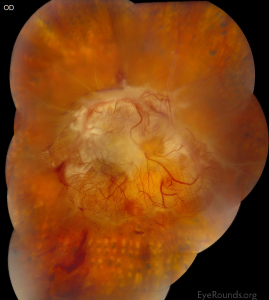

Diabetic eye disease